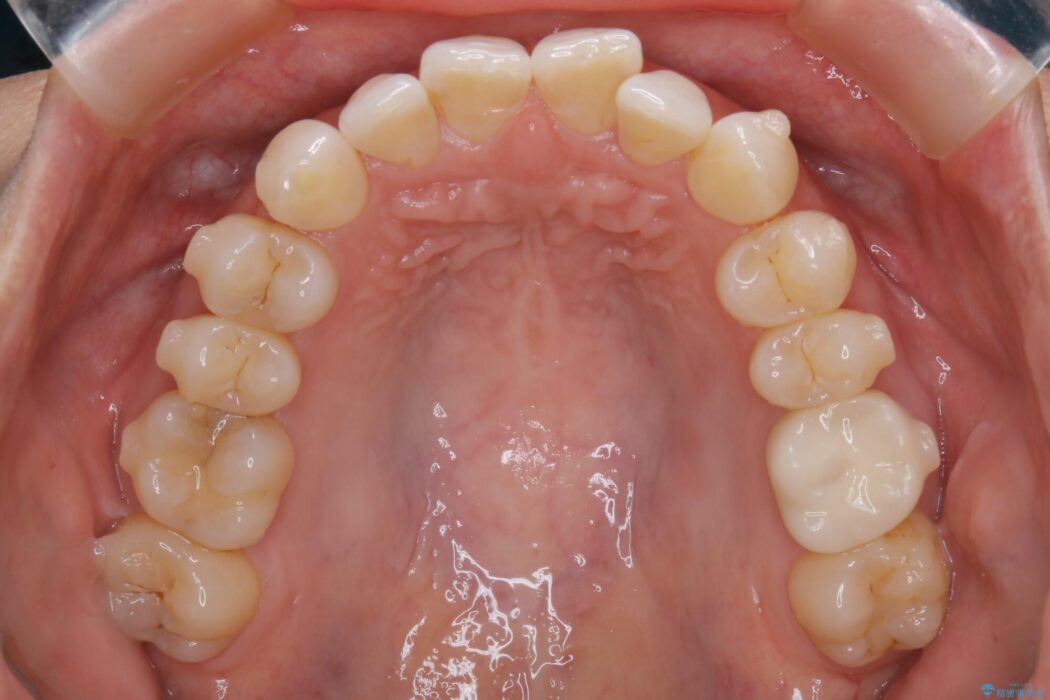

悪くなっている歯の放置はできないと判断しましたので、患者様と様々な治療プランを相談した上で、最終的に該当の歯は抜歯をして噛み合わせを改善し、その後インビザラインでの矯正治療を行うこととしました。

噛み合わせも改善され、一番最初の目的であった歯列もきれいに整いご満足いただけました。